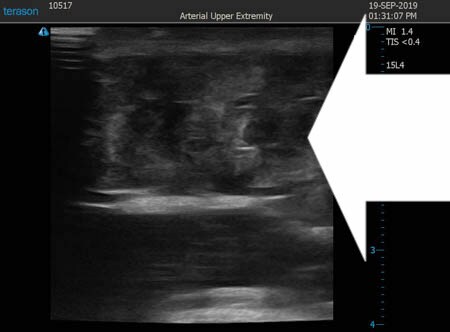

いつものように3Dタッチビュー(超音波)で

皮下脂肪層を評価してみましょう。

右二の腕